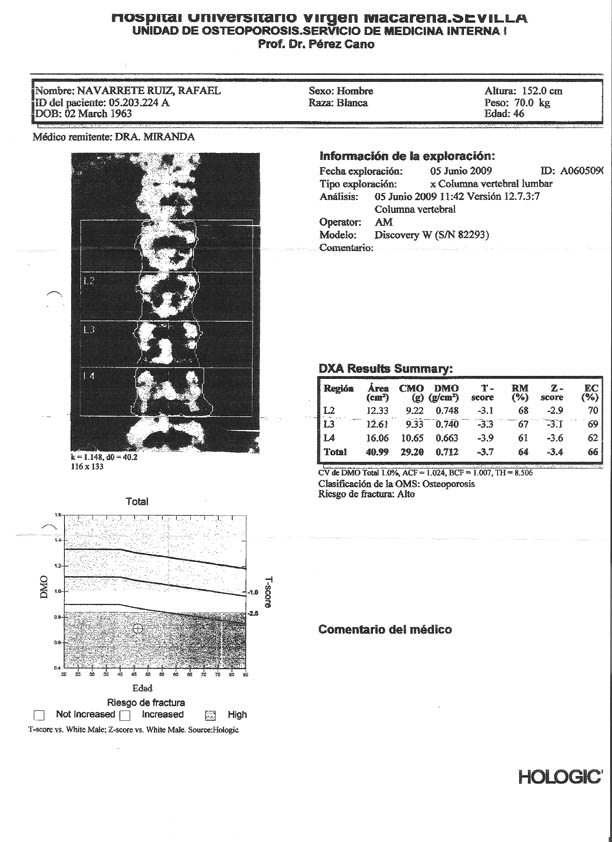

Densitometrías

Densidad ósea-Fémur 09 - Densidad en columna 09